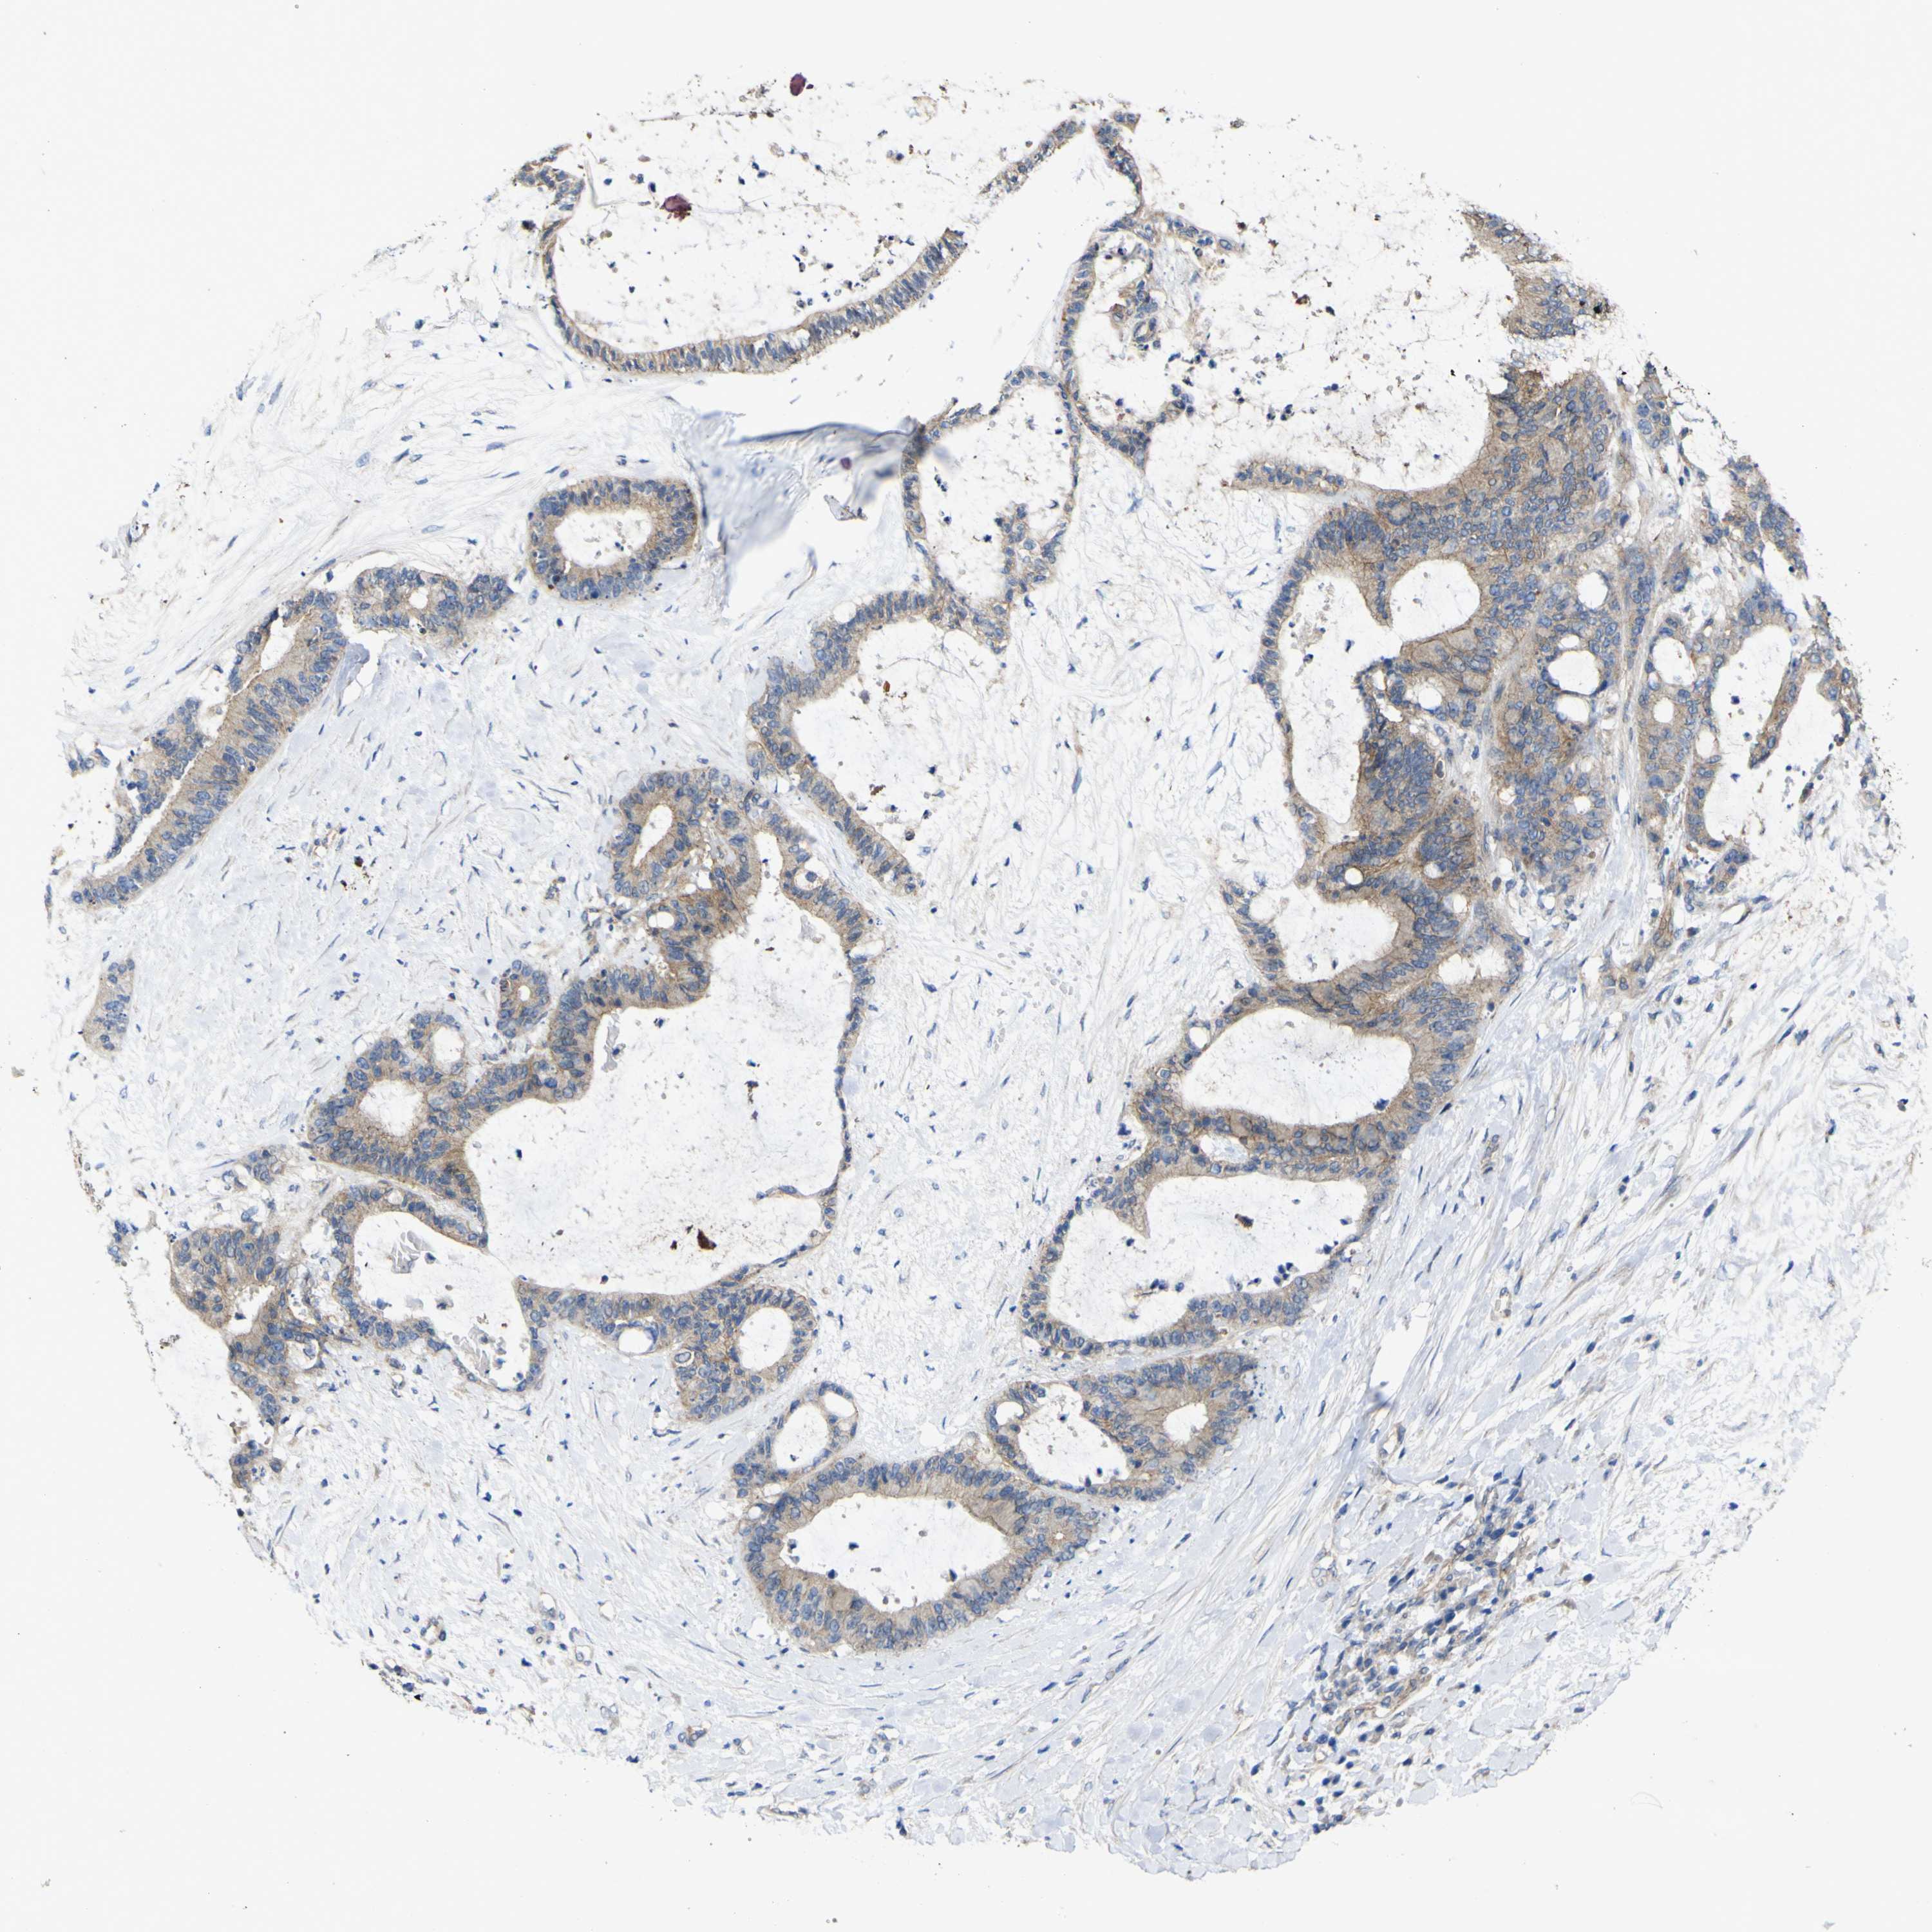

LIVER CANCER - Protein expressioni

A mouse-over function shows sample information and annotation data. Click on an image to view it in a full screen mode. Samples can be filtered based on level of antibody staining by selecting one or several of the following categories: high, medium, low and not detected. The assay and annotation is described here.

Note that samples used for immunohistochemistry by the Human Protein Atlas do not correspond to samples in the TCGA dataset.

Antibody stainingi

Antibody staining in the annotated cell types in the current human tissue is reported as not detected, low, medium, or high, based on conventional immunohistochemistry profiling in selected tissues. This score is based on the combination of the staining intensity and fraction of stained cells.

Each image is clickable and will lead to virtual microscopy that enables deeper exploration of all samples and also displays staining intensity scores, fraction scores and subcellular localization as well as patient and tissue information for each sample.

Antibody HPA012948

Staining

High

Medium

Low

Not detected

Intensity

Strong

Moderate

Weak

Negative

Quantity

>75%

75%-25%

<25%

None

Location

Nuclear

Cytoplasmic/membranous

Cytoplasmic/membranous,nuclear

Cholangiocarcinoma

Carcinoma, Hepatocellular, NOS